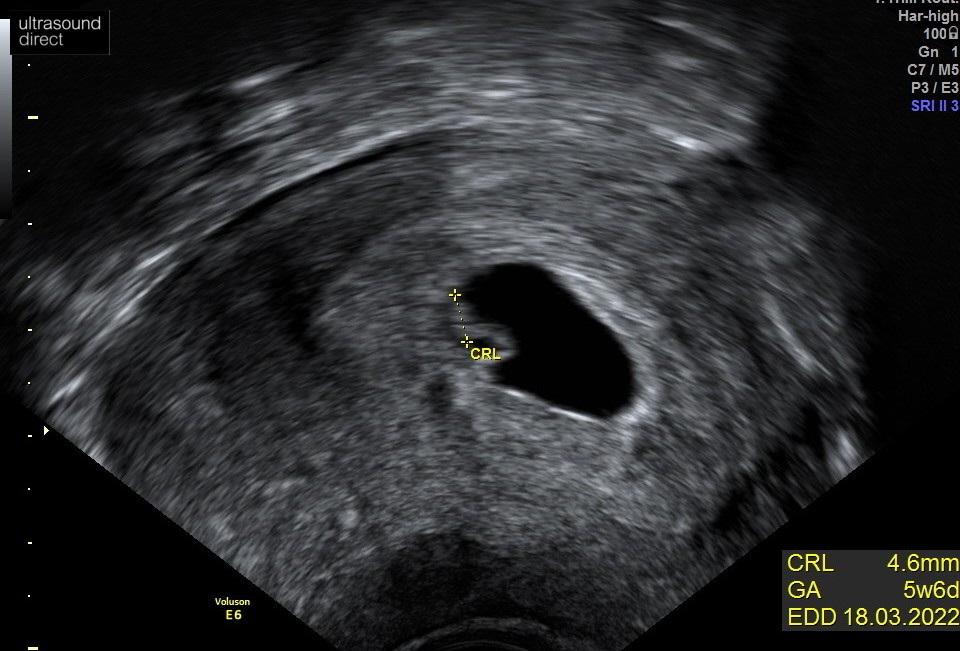

zazdroszczę! U ciebie 5+6 i serduszko a u mnie nawet zarodka nie maWlasnie wrocilam do domu. Widzialam serduszkoCiaza wyglada niestety na 5 dni mlodsza, a wiem, ze maks 2-3 dni roznicy jest mozliwe. Pocieszam sie, ze to moze byc wina slabego usg. CRL wyszlo 4.6mm i wiek obliczyla na 5+6, czyli dokladnie tak samo jak w ciazy, ktora stracilam w 8 tyg. Dobrze, ze za tydzien mam usg w szpitalu, wydaje mi sie, ze mieli duzo lepszy sprzet, a i lekarka byla duzo dokladniejsza niz ta prywatnie. W ogole zaczela usg przez brzuch nie wiem na cholere w tak wczesnej ciazy. Kazalam jej przerwac tak mocno mi brzuch uciskala. Teraz boli mnie lewy jajnik :/ Boje sie, ze tym uciskaniem mogla mi krwiak naruszyc, nie wiem czy to mozliwe, ale tak jak wczesniej mnie brzuch nie bolal tak teraz boli

Super wygląda na to że jest okWlasnie wrocilam do domu. Widzialam serduszkoCiaza wyglada niestety na 5 dni mlodsza, a wiem, ze maks 2-3 dni roznicy jest mozliwe. Pocieszam sie, ze to moze byc wina slabego usg. CRL wyszlo 4.6mm i wiek obliczyla na 5+6, czyli dokladnie tak samo jak w ciazy, ktora stracilam w 8 tyg. Dobrze, ze za tydzien mam usg w szpitalu, wydaje mi sie, ze mieli duzo lepszy sprzet, a i lekarka byla duzo dokladniejsza niz ta prywatnie. W ogole zaczela usg przez brzuch nie wiem na cholere w tak wczesnej ciazy. Kazalam jej przerwac tak mocno mi brzuch uciskala. Teraz boli mnie lewy jajnik :/ Boje sie, ze tym uciskaniem mogla mi krwiak naruszyc, nie wiem czy to mozliwe, ale tak jak wczesniej mnie brzuch nie bolal tak teraz boli